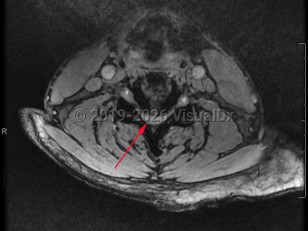

Cervical spinal stenosis

Cervical spinal stenosis is the narrowing of the spinal canal in the neck. Asymptomatic spinal stenosis may be discovered incidentally on imaging, but when it causes impingement of the spinal cord or nerve roots, symptoms can include weakness of the extremities, numbness / paresthesias, and neuropathic / radicular pain.

Narrowing of the cervical spinal canal can result in myelopathy that will result in upper motor neuron signs, such as hyperreflexia, especially in the lower extremities. Patient may experience walking difficulties or ataxia. Neck pain is common. Narrowing of the neural foramina in the cervical spine will often cause a radiculopathy. Compression of the cervical nerve roots can result in lower motor neuron signs in the upper extremities, which may result in muscle atrophy and fasciculations. Symptoms typically worsen with extension of the spine and improve with flexion.